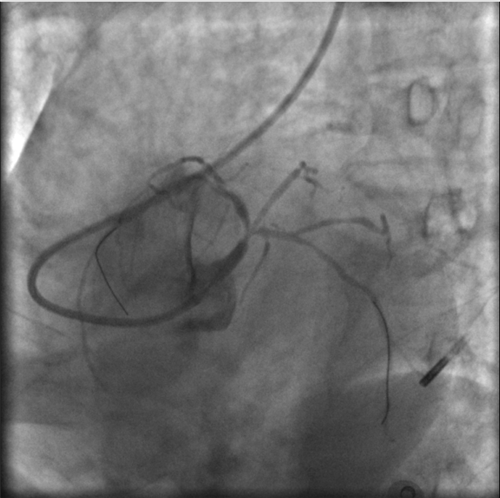

根據(jù)IVUS檢查結(jié)果,在前降支近中段至左主干植入3枚支架,充分?jǐn)U張后,狹窄完全解除,血流恢復(fù)通暢。

植入3枚支架,血流恢復(fù)通暢